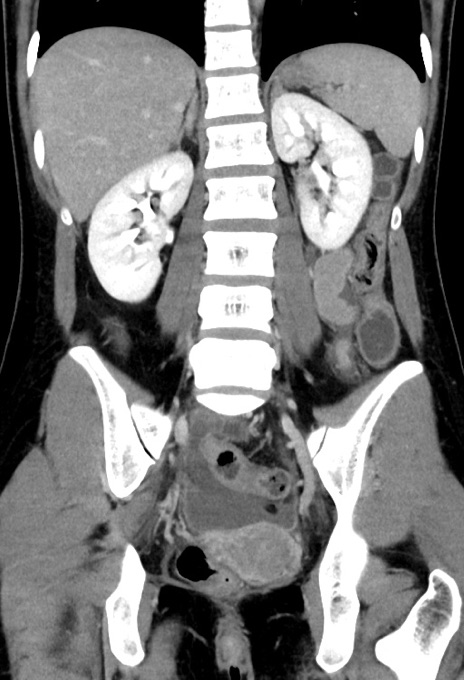

症例17(冠状断像)

【症例】20歳代女性

【主訴】嘔吐、下腹部痛

【現病歴】昨日夕食後に嘔吐し下腹部痛が出現。本日になっても嘔吐持続し改善しないため来院。

【身体所見】意識清明、BT 37.2℃、BP 108/67mmHg、腹部:平坦、やや硬、下腹部正中から右にかけて圧痛あり、反跳痛軽度あり、tapping pain(+)。

【データ】WBC 13600、CRP 14.94